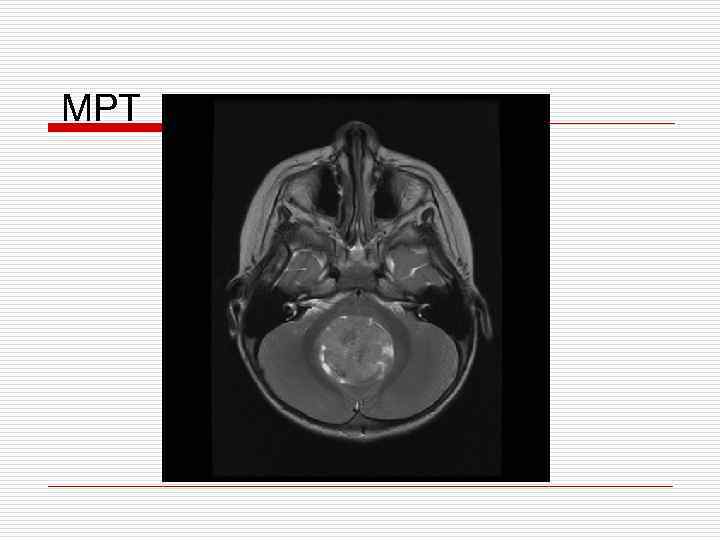

Клинический пример o Девочка В. , 13 лет – атаксия в течении 1 месяца o В течении 2 недель нарастание головных болей o Рвота по утрам n Темпиратура тела нормальная n Нет изменений в ОАК, ОАМ и БХ; педиатр исключает соматическую патологию

МРТ

Опухоли головного мозга у детей Морфологически гетерогенны * клетки-предшественники: glial, neural, other, combination * локализация: ЗЧЯ: 50% супратенториально: 50% * Клиника зависит от: локализации возраста

Опухоли мозга у детей o Инфратенториальная локализация 50% чаще < 6 лет o Супратенториальная локализация 50% чаще > 8 лет